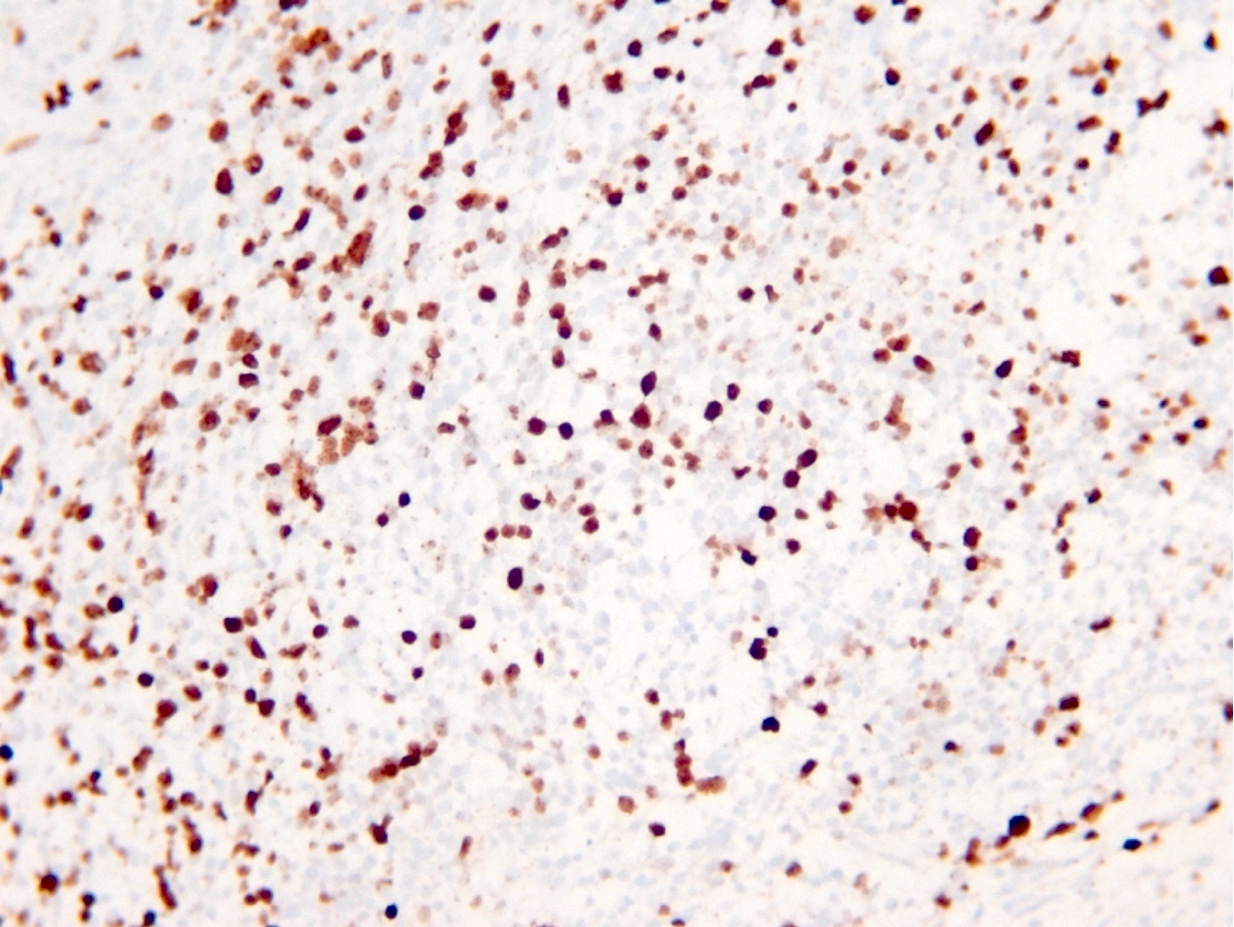

Microscopic (histologic) images

Contributed by Eman Abdelzaher, M.D., Ph.D., John DeWitt, M.D., Ph.D. and Meaghan Morris, M.D., Ph.D.

Which of the following is true about the entity in the figure above presenting in a 50 year old man?

B. If R132H IDH1 immunohistochemistry is positive, ATRX staining of tumor cells is expected to be lost. The image is consistent with an infiltrating astrocytoma with significant pleomorphism and mitotic activity. If R132H IDH1 immunohistochemistry is positive, as stated in answer B, the findings are then consistent with astrocytoma, IDH mutant, CNS WHO grade 3. Astrocytoma, IDH mutant tumors often show concurrent ATRX mutation, indicated by loss of staining in tumor cells with ATRX immunohistochemistry.